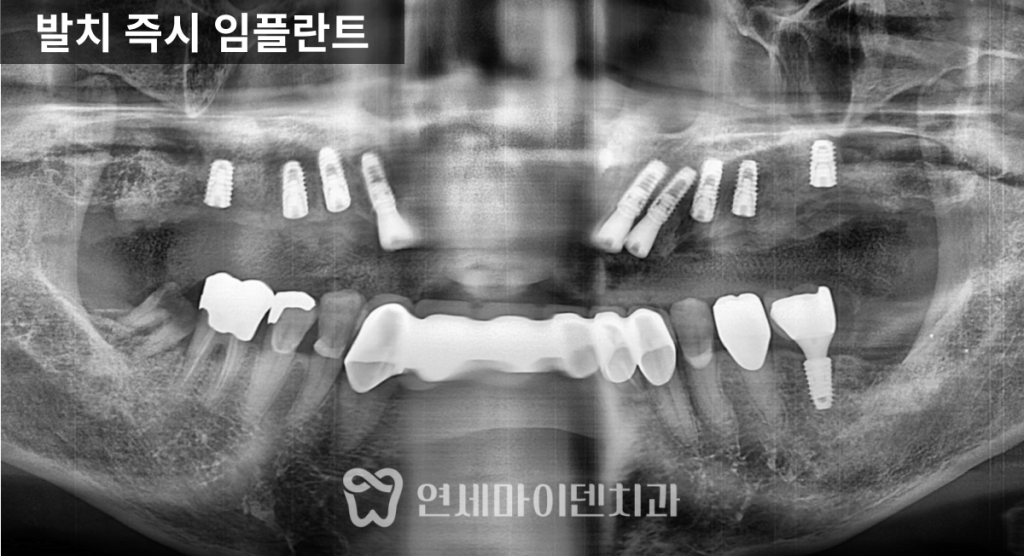

자연스럽게 맞물릴 수 있습니다.상악 임플란트 치료 과정

상악은 다수의 치아가

깊이 손상된 상태였기 때문에,

발치 후 임플란트 수복이 필요했습니다.상악 임플란트 치료 계획은

다음과 같이 수립했습니다.1. 송곳니 부위에 임플란트를 식립해

전방과 후방의 지지를 확보합니다.2. 앞니 4개 부위에 임플란트를 배치해

심미, 발음, 지지 기능을 형성합니다.3. 상악 큰어금니와 작은어금니 부위는

브릿지 임플란트 형태로 계획했습니다.보존이 가능한 치아는 살리고,

결손 부위는 임플란트와 브릿지의 조합으로

식사 시 충분한 기능을 확보하는 방향이었습니다.하악 임플란트 치료 과정

하악은 기존에

송곳니부터 반대편 송곳니까지

롱 브릿지 보철로 연결된 상태였습니다.하악 치료의 재설계 방향은 다음과 같았습니다.

1.기존 롱 브릿지를 분리합니다.

2.전치부 4개를 지지할 임플란트 2개를 배치합니다.

3.양쪽 송곳니는 개별 크라운으로 분리합니다.

이 과정을 통해

아래 앞니를 기존보다

조금 더 후방으로 재배치할 수 있었고,

송곳니는 개별 크라운으로 제작해

치실 사용이 가능하도록 하여

유지 관리성을 높였습니다.어금니 교합 설정 후 앞니 위치 조정